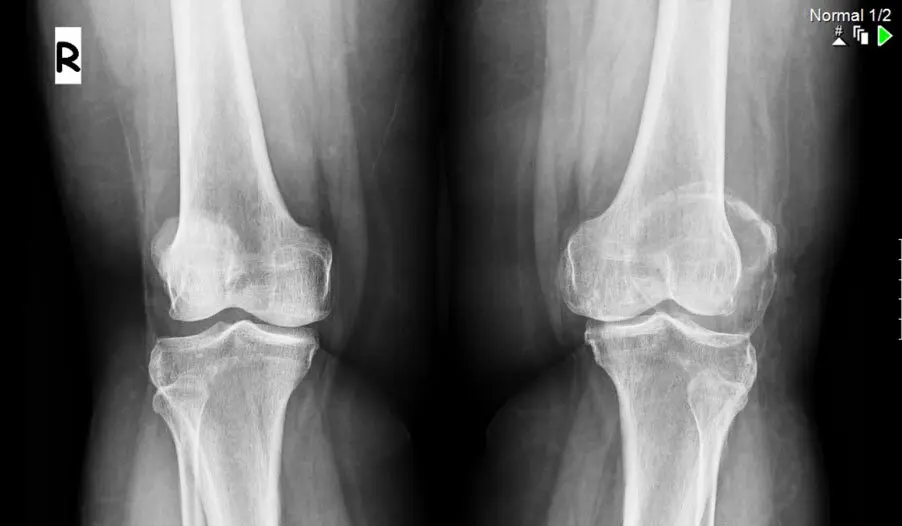

| Рентгенография шейного отдела | Это основной метод для подтверждения диагноза. Снимки в нескольких проекциях (прямой, боковой, с функциональными пробами) позволяют увидеть сросшиеся позвонки, оценить их количество и локализацию, выявить нестабильность позвоночных сегментов. |